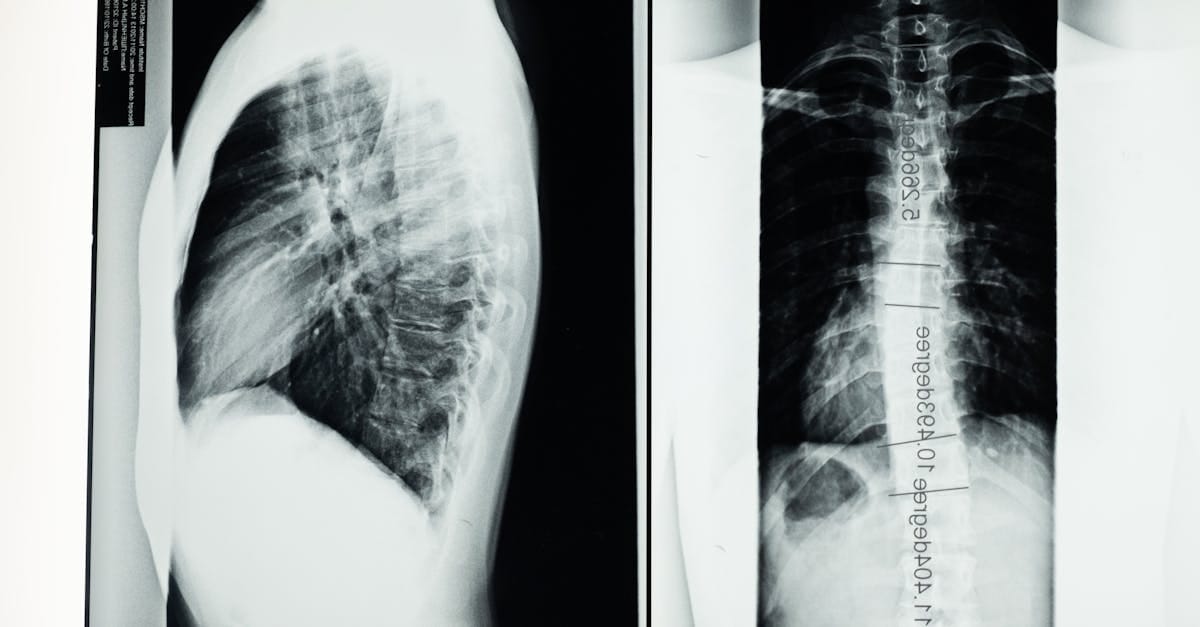

Source of Pain: Compressed or dehydrated intervertebral disc

Understanding the Compressed Disc

An intervertebral disc can undergo deformation or compression, causing various ailments. This can occur due to various factors such as age-related wear, an injury, or poor posture. When the disc is compressed, it can lead to chronic pain and difficulties in performing daily activities.

Intervertebral discs play an essential role in the body’s health. Located between the vertebrae, they act as shock absorbers, absorbing impacts and maintaining the flexibility of the spine. A disc can become compressed due to various factors, including wear and tear, injuries, or incorrect movements. When this happens, the disc loses its ability to function properly, which can lead to intense pain, numbness, and difficulties in moving.